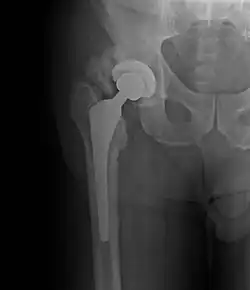

Heterotopic ossification around the hip joint in a patient who has undergone hip arthroplasty

Heterotopic ossification of varying severity can be caused by surgery or trauma to the hips and legs. About every third patient who has total hip arthroplasty (joint replacement) or a severe fracture of the long bones of the lower leg will develop heterotopic ossification, but is uncommonly symptomatic. Between 50% and 90% of patients who developed heterotopic ossification following a previous hip arthroplasty will develop additional heterotopic ossification.